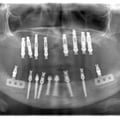

Імплантація 16,17,18 без врахування жодних правил оклюзії та знань в імплантології